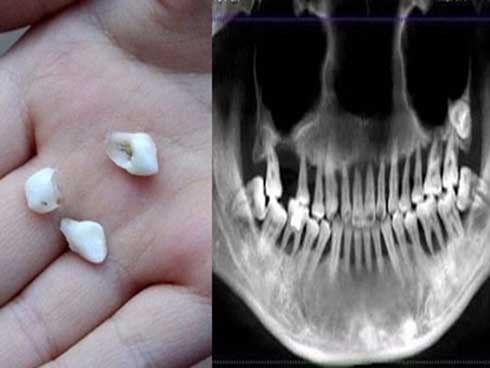

Cô gái 28 tuổi rụng răng, móm mém như cụ bà 80 vì thói quen xấu

Một cô gái 28 tuổi lại có bộ răng móm mém, lỏng lẻo như một bà cụ, mất toàn bộ chức năng nhai thức ăn.